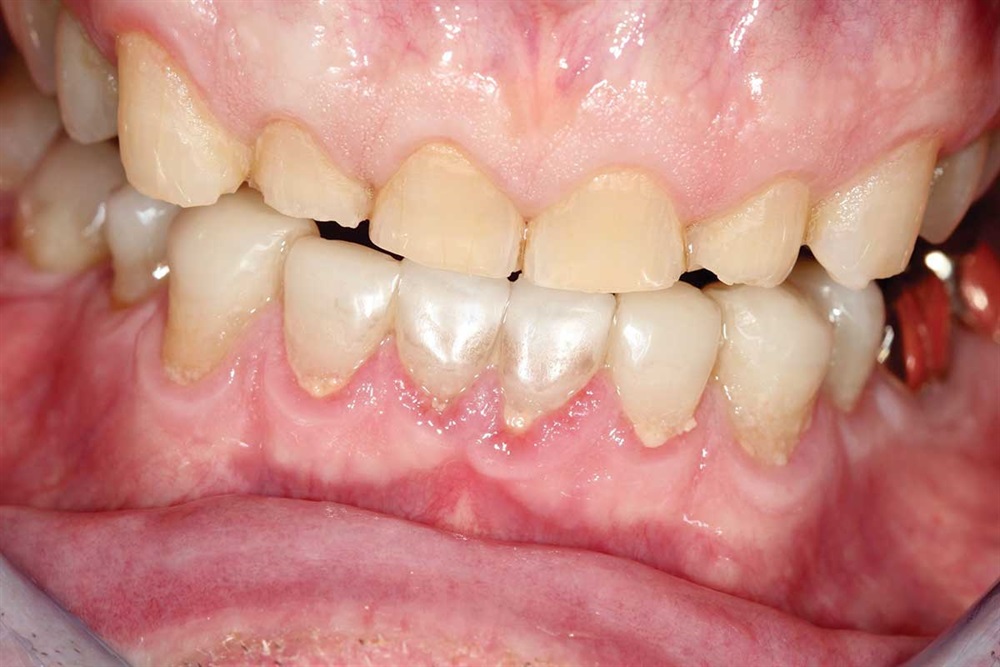

Fig. 14–16: It is hard to see, but the patient’s bicuspids nearly miss in occlusion because the upper bicuspids are buccal to his lower bicuspid. One reason for ortho would have been to expand the lower arch to get more occlusion on the bicuspids.

Show Your Work

Fig. 15

Fig. 16